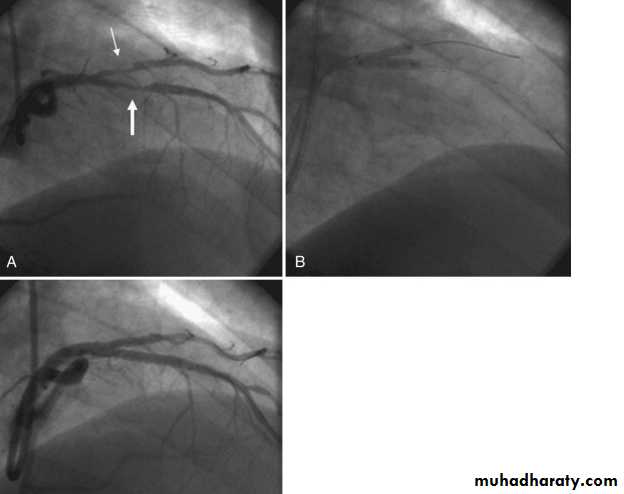

Coronary Angiography

Gold standard to diagnose I.H.D. until now

Demonstrates the anatomy of the artery. By showing

1- severity of stenosis and type of the lesion

a- non-significant stenosis (<70%)

b- Mod or severe (Critical) lesion ( >70% )

2- Extent of the disease:-

single, two ,three vessel disease, Left main

stem disease (> 50%)

3- L.V angiography if done will assess L.V. function

4- If suitable intervention can be done

Indicated for the diagnosis of atypical chest pain

and before revascularization

Severe proximal LAD Lesion

Very severe proximal LAD stenosis

Total CX Occlusion